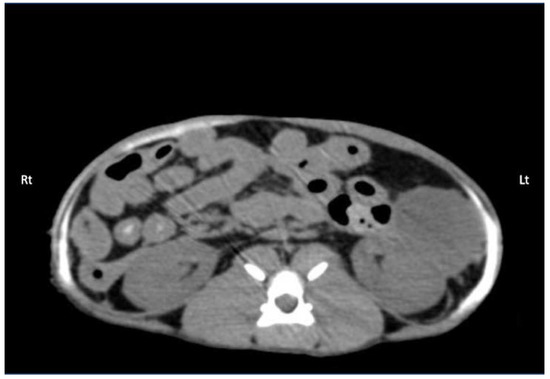

Contrast solution was identified in the target fascial plane in eight TAP-L and eight TAP-SL (Figure 7). Following all 16 lateral TAP injections, the contrast solution distribution was assessed as “possible partial intramuscular infiltration in the m. transversus abdominis” and following 7 out of 16 lateral TAP injections (3 TAP-L and 4 TAP-SL) as “possible focal spread between the mm. obliquus internus and externus abdominis”. Focal (1.5 mm) intraperitoneal contrast solution was observed following two lateral TAP injections (1 TAP-L and 1 TAP-SL). In 2 TAP-SL, contrast solution was observed within the falciform ligament fat (Figure 8a). Contrast solution was not observed in the abdominal cavity or organs.

Figure 7. Computed tomography (CT) image showing the distribution of 0.5 mL/kg bupivacaine–iopamidol–dye solution administered by two approaches of the TAP injection in a cat; a TAP-L injection was performed in the left (Lt) hemiabdomen and a TAP-SL in the right (Rt) hemiabdomen; WL 50, WW 350. Ventral is at the top of the image.